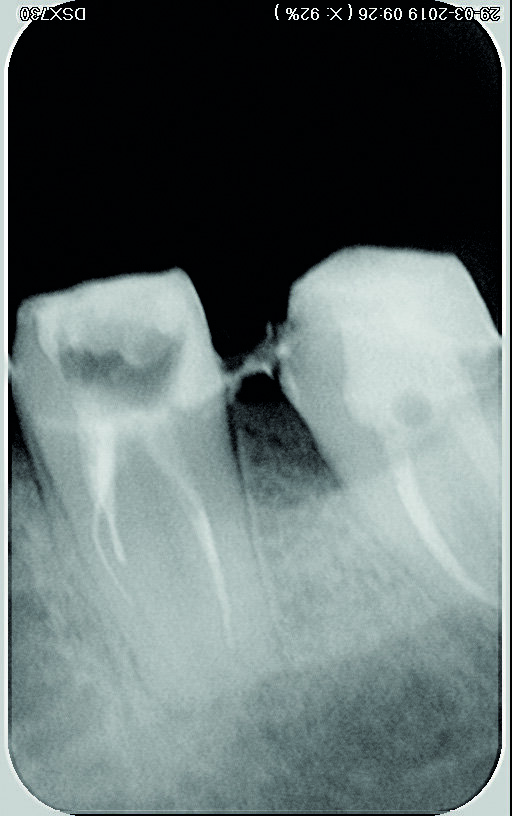

Une femme de 44 ans, sans antécédents médicaux particuliers, nous est adressée pour le retraitement endodontique de sa première molaire inférieure gauche qui cause une douleur depuis une semaine. La dent est très sensible à la percussion, ne présente aucune mobilité, et le résultat du sondage parodontal se situe dans les limites physiologiques. Une première radiographie est prise (Fig. 1). Elle montre trois fragments d’instruments fracturés demeurés dans deux canaux (mésial et distal) après le traitement endodontique précédent, ainsi que des signes d’une pathologie péri-apicale. Les résultats des examens cliniques et radiographiques conduisent à un diagnostic de parodontite apicale symptomatique de la dent déjà traitée et suggèrent la nécessité d’un retraitement.

Fig. 1 : Radiographie initiale.

Fig. 5 : Radiographie après retrait de la partie coronaire de gutta-percha et création d’une plate-forme de travail

Fig. 13 : Radiographie après retrait du fragment.